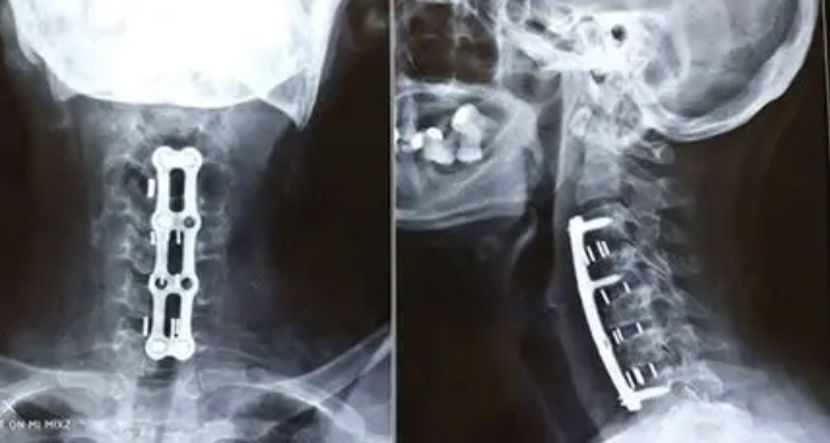

After Surgery Results

ACDF (Fusion)

Anterior Cervical Discectomy and Fusion to remove a damaged disc and fuse vertebrae.

Anterior Approach

Procedure typically performed through the front of the neck for better access.